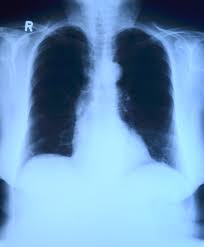

4) 정기검진

특히 흡연력 있는 40세 이상 성인은 저선량 CT 검진을 권장합니다.